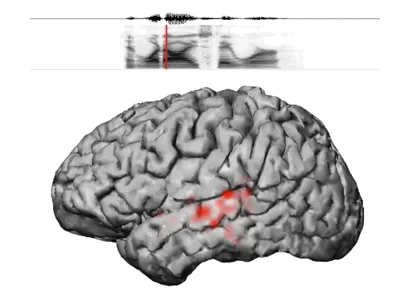

The patients listened to a collection of 500 unique English sentences spoken by 400 different people while the researchers recorded from a brain area called the superior temporal gyrus (STG; also known as Wernicke’s area), which previous research has shown to be involved in speech perception. The utterances contained multiple instances of every English speech sound.

Many researchers have presumed that brain cells in the STG would respond to phonemes. But the researchers found instead that regions of the STG are tuned to respond to even more elemental acoustic features that reference the particular way that speech sounds are generated from the vocal tract. “These regions are spread out over the STG,” Mesgarani explains. “As a result, when we hear someone talk, different areas in the brain ‘light up’ as we hear the stream of different speech elements.”

The articulation of each plosive creates an acoustic pattern common to the entire class of these consonants, as does the turbulence created by fricatives. The researchers found that particular regions of the STG are precisely tuned to robustly respond to these broad, shared features rather than to individual phonemes like b or z.